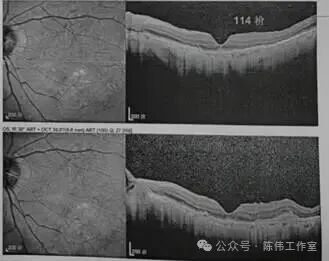

陈伟院长根据老人详尽的眼底检查结果,为他的右眼量身定制了第一步“光明攻略”——抗VEGF治疗。这是一种通过眼内注射药物,“狙击”导致黄斑水肿的异常血管因子的方法。一个疗程结束,复查结果较为理想:黄斑水肿由原来的348降至114。

地基稳固了,下一步就是清除那层厚厚的“障眼迷雾”。陈伟院长结合林大爷的日常生活习惯和用眼需求,精心设计了第二步方案:通过屈光白内障手术植入一枚高品质的人工晶体。手术室的无影灯下,陈伟院长操作娴熟,一枚透明的人工晶体被稳稳地植入囊袋。